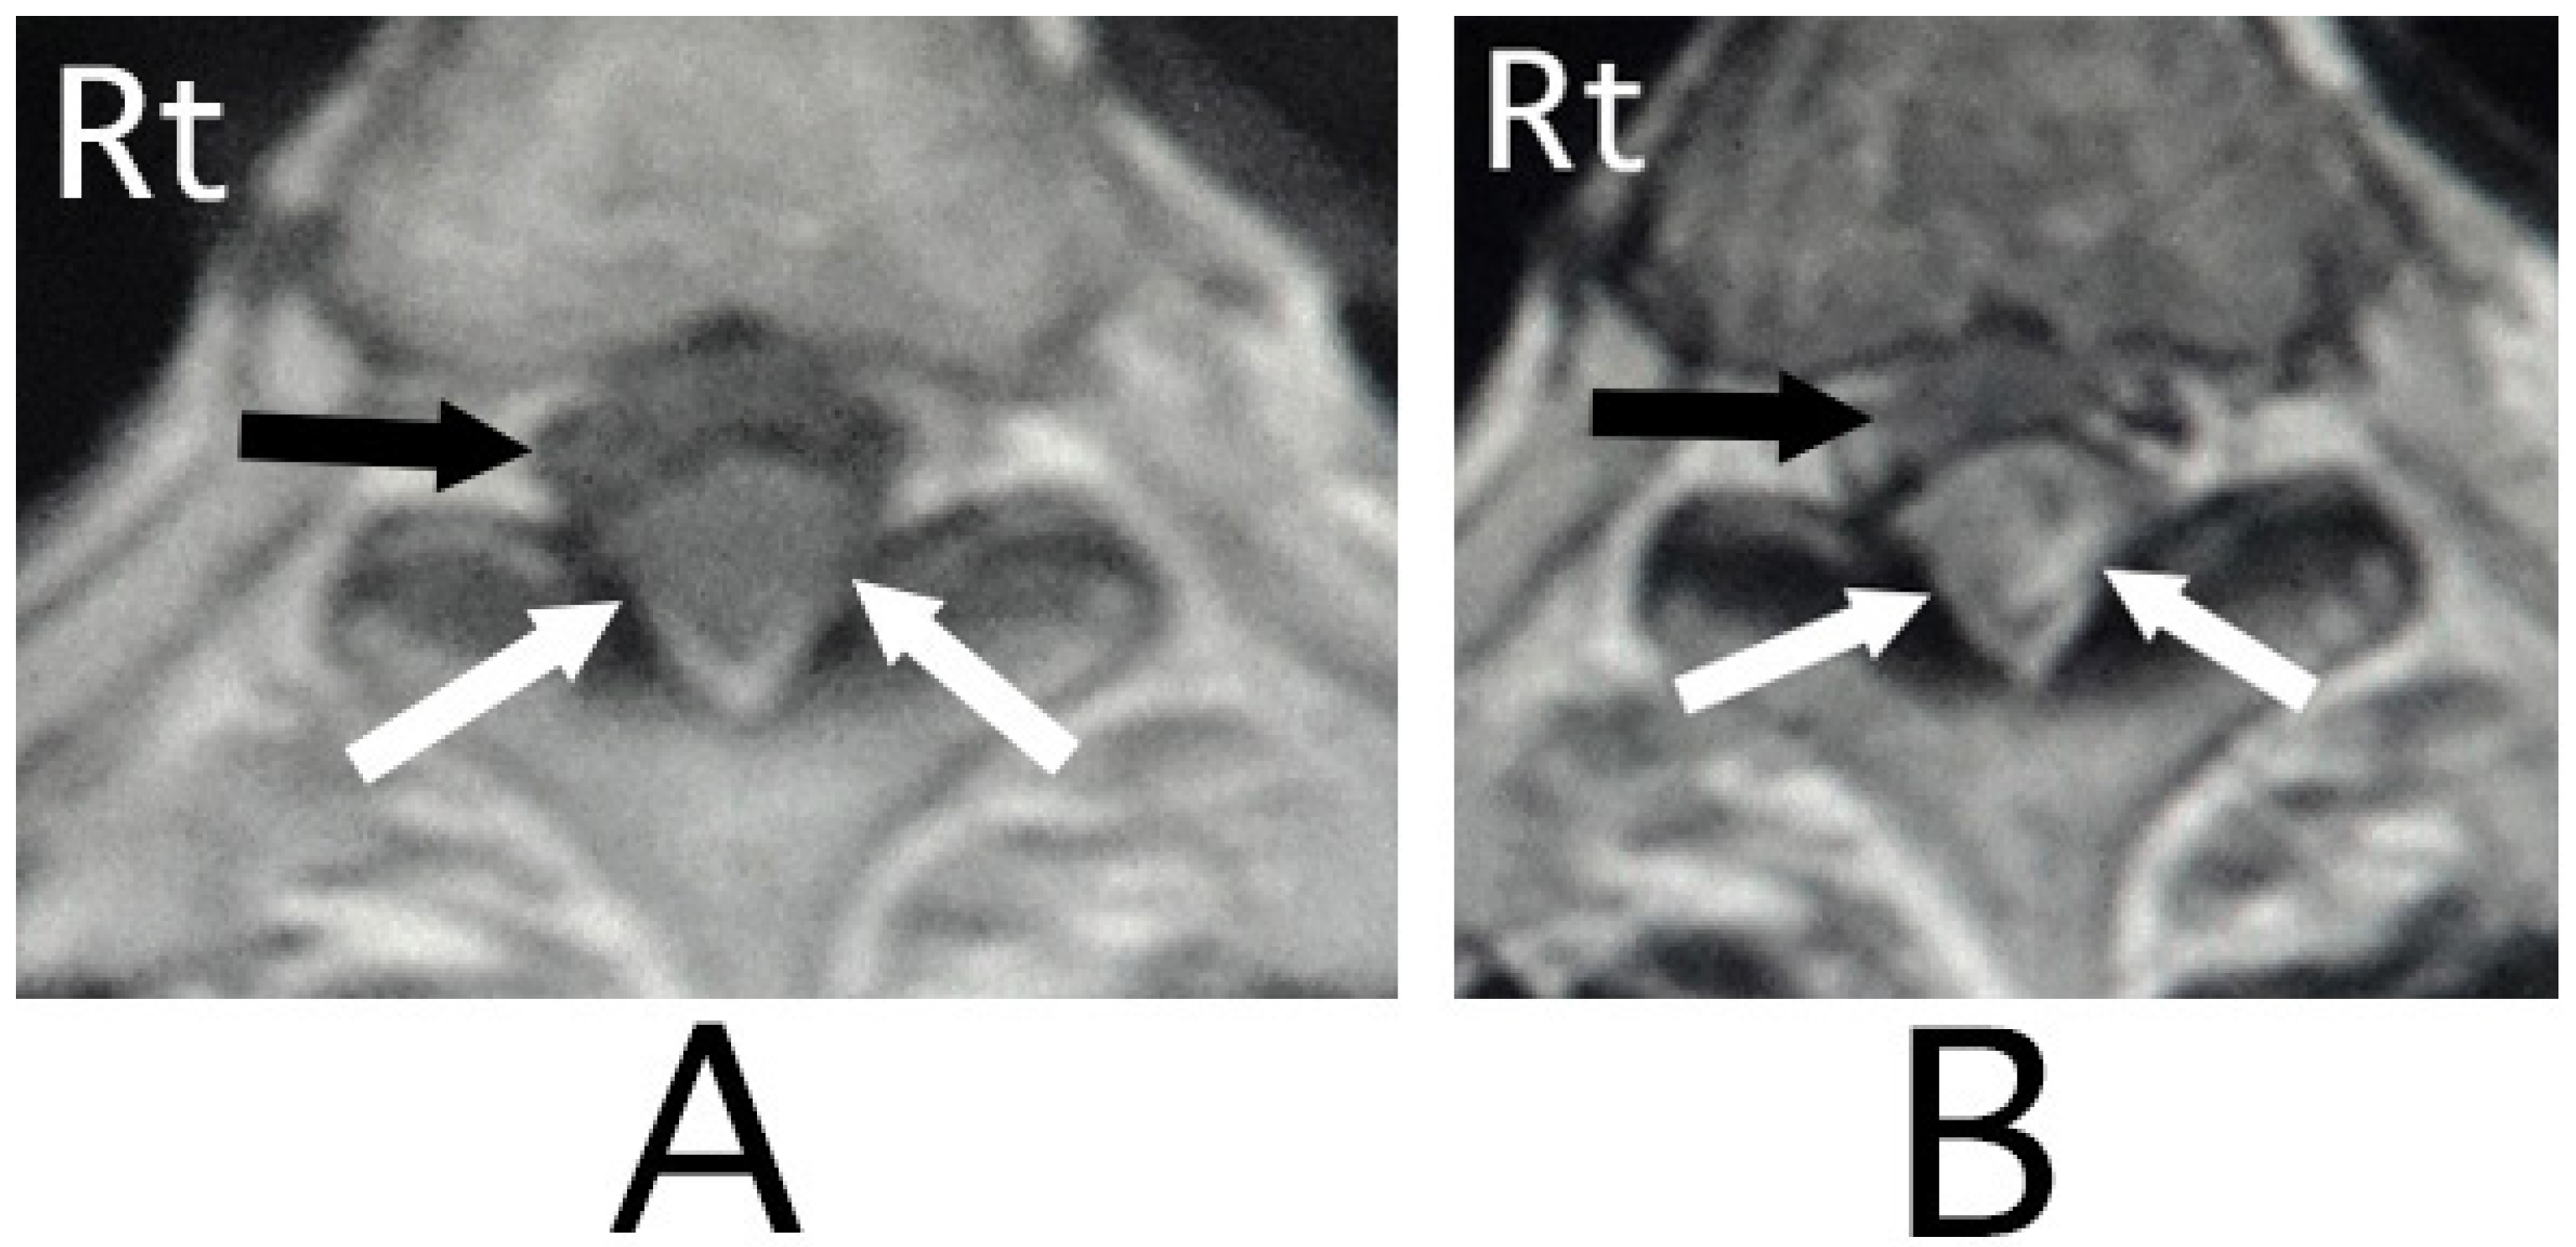

The lesion in the intracranial region or the cervical spinal cord was suspected. Computed tomography (CT) images of the head and X-ray of the cervical bone were normal; however, sagittal CT images of the cervical bone showed a slightly abnormal high-density area (HDA) behind the spinal cord at the level between C4 and C7 (Figure 3A). This abnormal HDA was located in the posterior part on the right side in axial CT images (Figure 3B). MRI analysis was performed because the presence of a hemorrhagic lesion was suspected, based on the CT findings of the cervical bone. Sagittal T1-weighted MRI showed an iso-intensity mass in the epidural space behind the spinal cord at the level from C4 to C7 (Figure 4A). The lesion was noted as a heterogeneous high-intensity mass in sagittal T1-weighted images (Figure 4B). Axial T1-weighted MRI showed an iso-intensity mass in the posterior part on the right side in the epidural space and mild compression of the spinal cord (Figure 5A). The lesion was noted as a heterogeneous high-intensity mass in axial T2-weighted images (Figure 5B).

Figure 3. CT images of the cervical bone. CT images of the sagittal position showed a slight high-density mass behind the spinal cord at the level between C4 and C7 (black arrows) (A). The mass was located diagonally posterior part on the right side (black arrows) (B). (Rt = right).